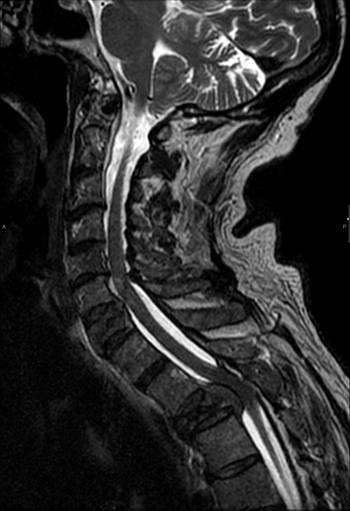

Imagen 2: Hígado con múltiples metástasis hepáticas y lesión estenosante de sigma.